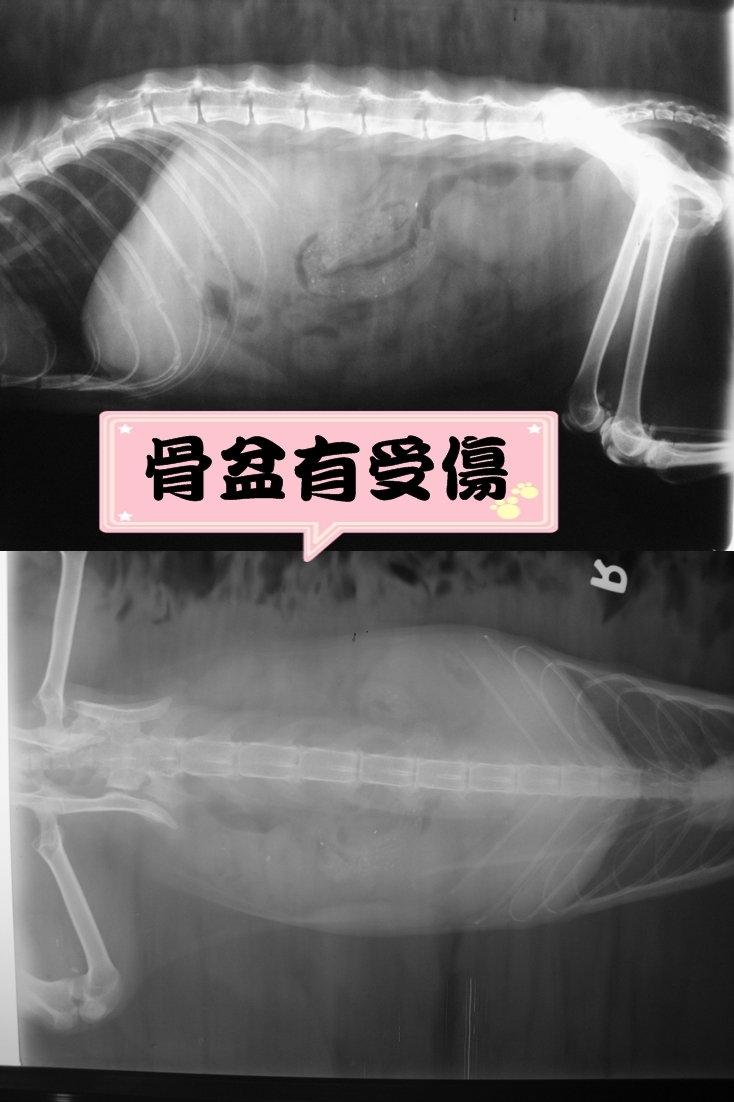

主題: 七賢路 難產的母貓 申請者姓名: 劉素鳳 花色: 申請日期: 2013-12-18 07:25:04 申請者部落格: 申請者臉書網址: 所在縣市/合作醫院: 高雄市/樂生動物醫院 治療費用: 11610元 需求人數: 13人 已結案 (2014-01-10 17:51:19) 報名人員: Pomela Kao(已付款)、Ju Hsiu Jao(已付款)、Bear(已付款)、Norman Wu(已付款)、Crystal Lin(已付款)、Adelaide Chen、Ping Meng(已付款)、Ping Meng(已付款)、學姐(已付款)、學姐、阿玲玲(已付款)、Shumi Tsai(已付款)、Jocelyne YuYu Kao(已付款)、sharonhuang9(已付款)、Freesia Tsai(已付款)、 候補人員: 動物病情說明: 這是在七賢路聽居民說快一週了, 看到一隻母貓生不出了,小貓的四腳出來但身體卡住還是母貓的體內,母貓就一直這樣帶著生不出來的小貓在身上, 看到的人都嚇壞了, 好幾位志工也幫忙來找, 但又找不到母貓的蹤影, 連續好幾天跑好幾趟, 終於發現這隻母貓了, 但卡在身上的小貓已經不見, 不確定是否裡肚子裡是否還有沒生出來的小貓, 也因為母貓已沒食慾也沒什麼力氣所以用網的抓住她, 趕緊送到醫院檢查. 動物近況說明: 檢查後醫生說肚內已經沒有看到有小貓, X光片看來母貓的骨盆有受傷斷掉, 不知是不是這樣造成難產, 還有一點是母貓有脫水及肝腎指數異常,且有口腔潰瘍及嚴重齒炎, 所以沒食慾也有可能是口炎造成, 幫她治療口炎拔掉多顆壞牙, 治療到恢復了精神和食慾, 再幫她做結紮, 目前健康出院了喔. 感謝所有幫忙的朋友.